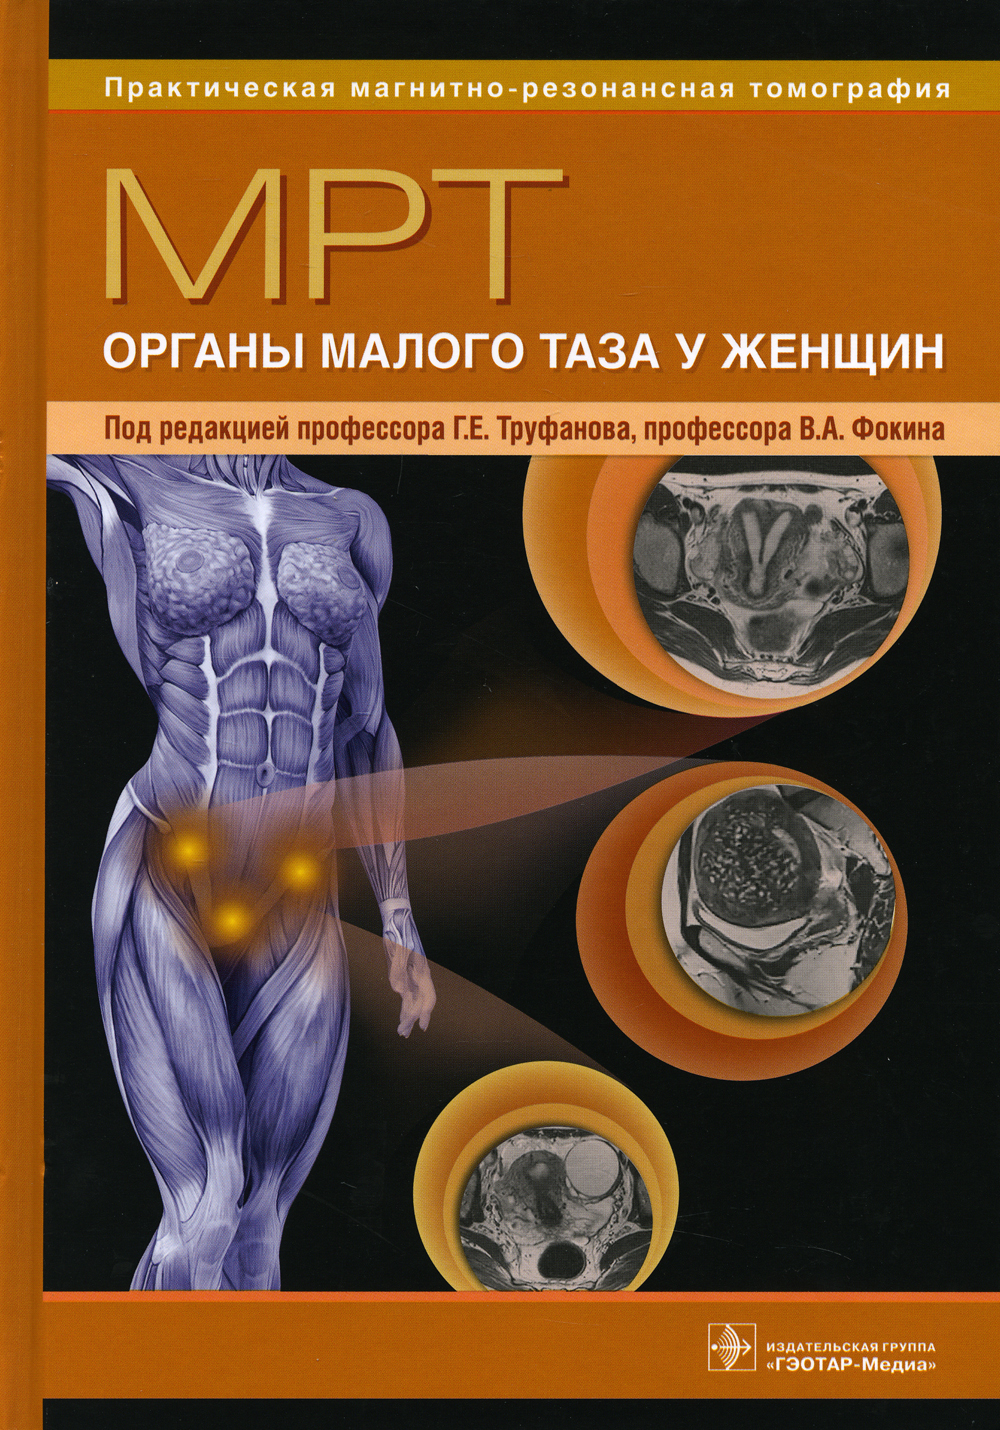

Мрт книги

Мрт малый таз